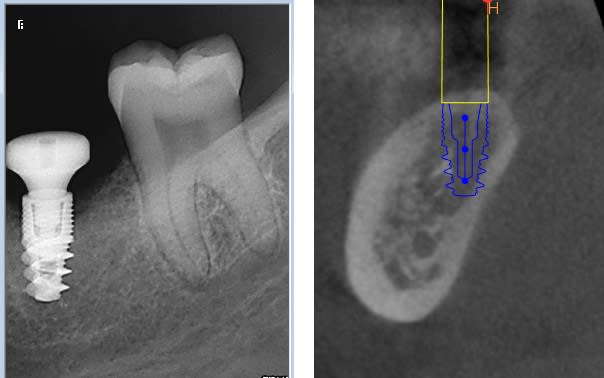

je ne comprends pas trop pourquoi, j'ai une perte osseuse a un mois, alors que le cas le semblait pas particulièrement compliqué.

implant placé légèrement infra osseux ( pas assez , sans doute, juste 0.5 mm ), couple 35 Nm, et vis de cica dans la séance.

on est a un mois et demi post op.